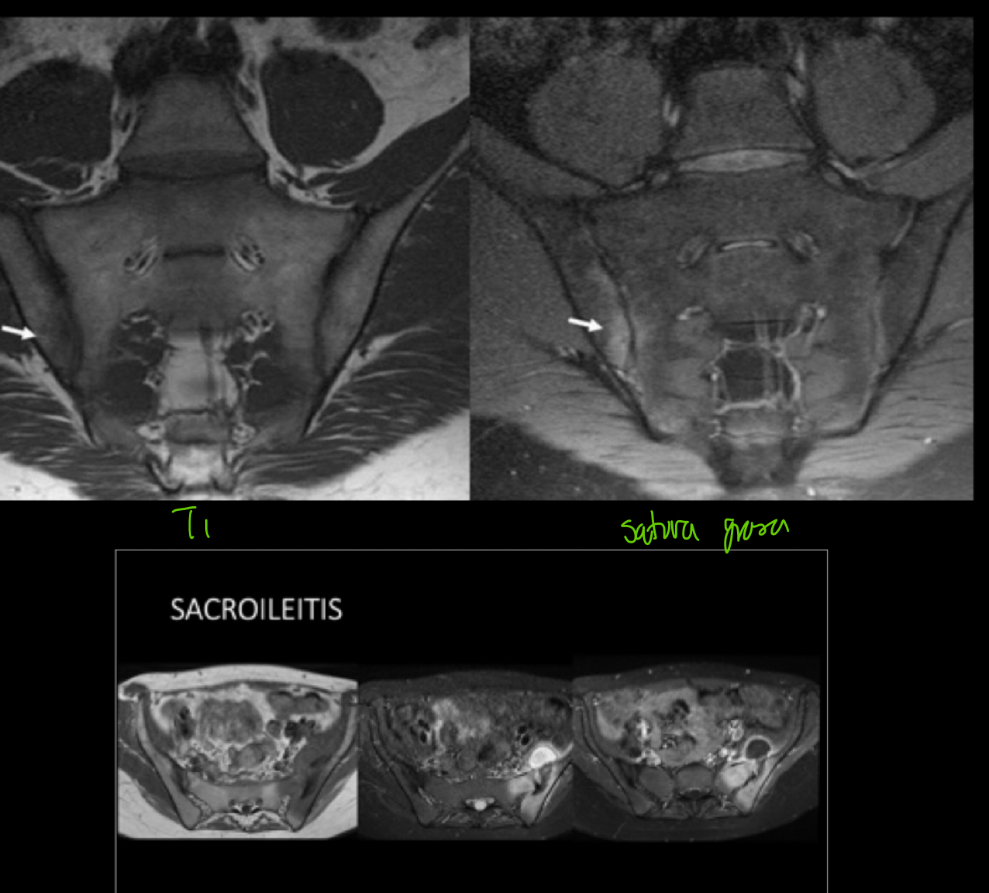

Q

q se ve en RM de sacroileitis

A

• lesiones peque

• Permite evaluar episodio agudo

• Evaluar involucro a otras estructuras

• Hiper en t2, fat sat, STIR

• Hipo t1

• Capta contraste